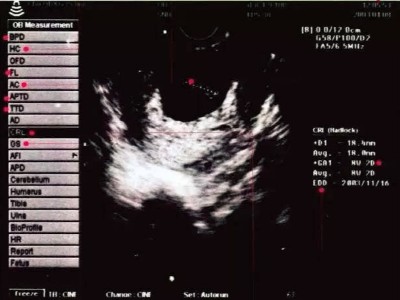

B超紙該如何看

當媽媽們拿到B超紙,B超紙該如何看呢-蘇州香蕉福利导航视频

媽媽們在懷孕期間一般情況下需要做4-5次的彩超檢查,每一次的檢查對於媽媽們來說都尤為重要,那麽,當媽媽們拿到B超紙時,看到上麵的一些專業詞,B超紙該如何看呢?下麵,小編就為大家來介紹一下。